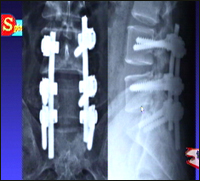

主持人:在腰部做手术风险大吗? 田伟:这是广大患者最为关心的问题,客观上讲都会有一定的风险性,但是随着医学技术的进步,这种风险性也在逐渐降低。从我们的实际工作情况来看这种手术并非十分危险。 刘波:这就是我们做了固定手术的一个病人的片子,从椎弓根打一些钉子,把三节腰椎进行一个固定,这种钛和金的材料不会对正常的活动产生不良影响,因此不必再次手术将它取出。手术过程同时进行血液的重吸收,因此目前有95%的患者在进行手术时已经不需要输血了。

主持人:术后需要长期的卧床休息吗? 田伟:过去手术由于没有一个很好的固定方法,因此术后必须要卧床很长时间等着骨头愈合。现在的这种内固定的方法技术变得相对先进,也改善了这些术后的不良因素,术后三天带上一个保护性的围腰就可以下地了,手术改进的一个很重要的目的就是要加快病人的康复。